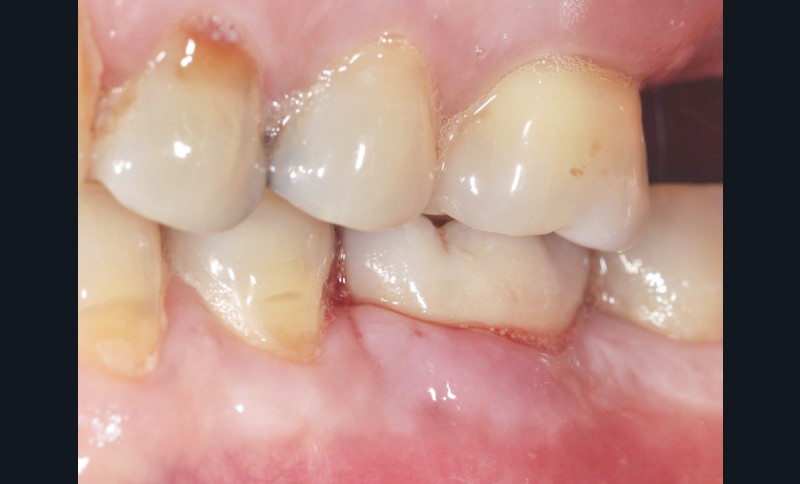

– la mucosite péri-implantaire, définie comme une inflammation réversible des tissus mous péri-implantaires sans atteinte osseuse (fig. 1a, b) ;